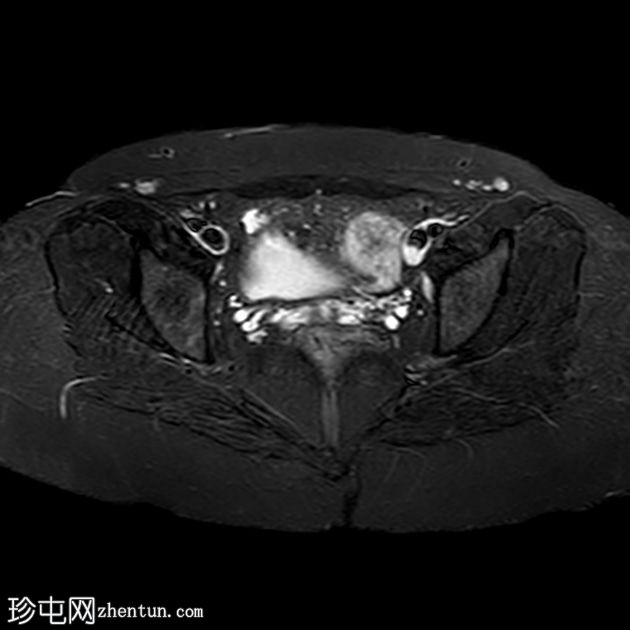

轴位

STIR序列

盆腔两侧可见两个残角,位于双侧卵巢尾侧。可见一条水平带连接两个残角。左侧残角呈腔状,右侧残角呈非腔状。

可见宫颈阴道发育不全,从两个残角延伸出少量发育不良的宫颈组织带。

本病例展示了一种 Mayer-Rokitansky-Küster-Hauser 综合征 (MRKH),其特征为子宫缺失和双侧残角;左侧子宫角呈腔状,右侧子宫角呈非腔状。子宫角位于盆腔两侧,双侧卵巢尾侧,并由一条水平带连接。该病伴有宫颈阴道发育不全。

MRKH 患者常常被误认为完全没有子宫。有时,患者存在残角,残角内可见管腔内积血或子宫腺肌症,提示子宫内膜功能尚存。